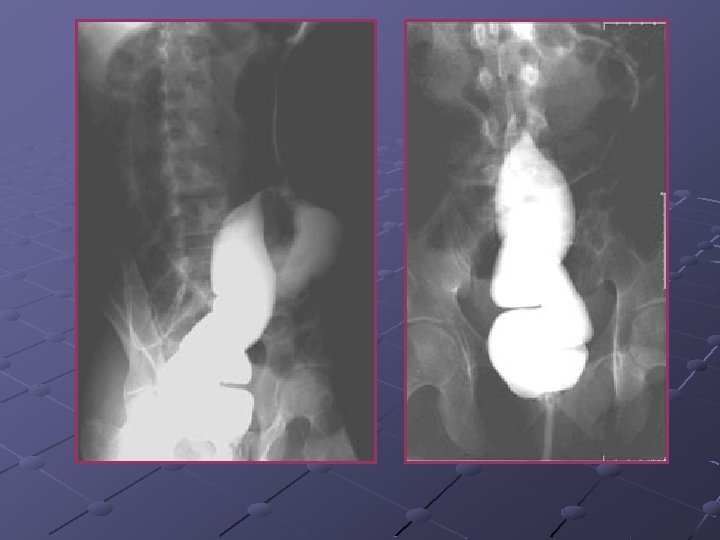

Cas n° 4 Garçon de 14 ans Porteur d’une maladie de Crohn Admis pour une poussée Pendant l’hospitalisation exacerbation des douleurs et distension abdominale

Mégacolon toxique Complication la + sévère des MII: col. ulcérative (1, 6 -13%), Crohn, Behcet, col. pseudomembraneuse amibiases, typhoïde, choléra Inflammat. suraiguë transmurale séreuse: perforation et/ou exsudation avec péritonite